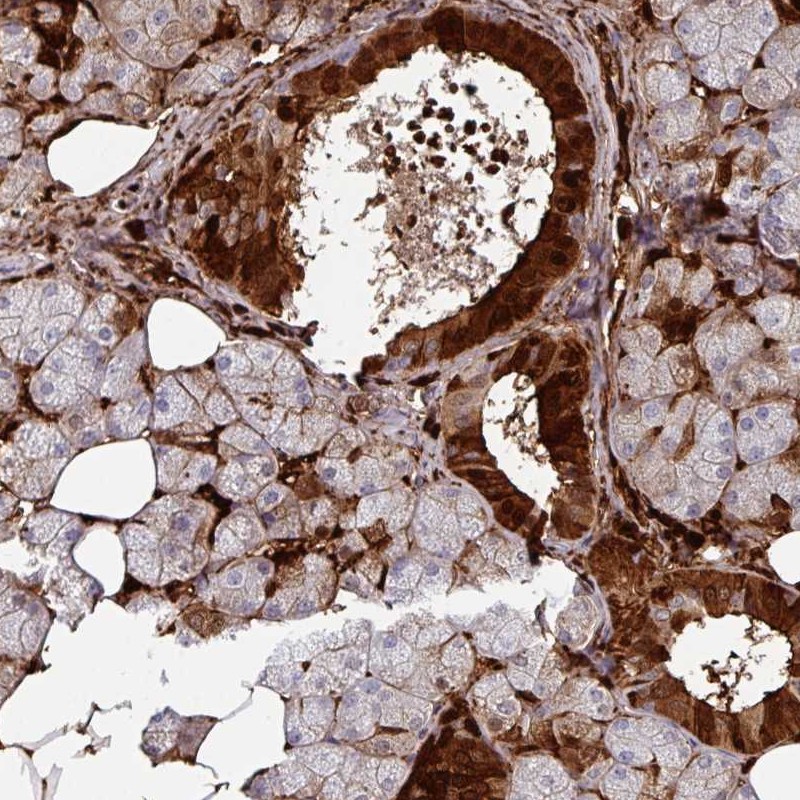

Immunohistochemical staining of human salivary gland shows strong cytoplasmic, nuclear and membranous positivity in glandular cells.